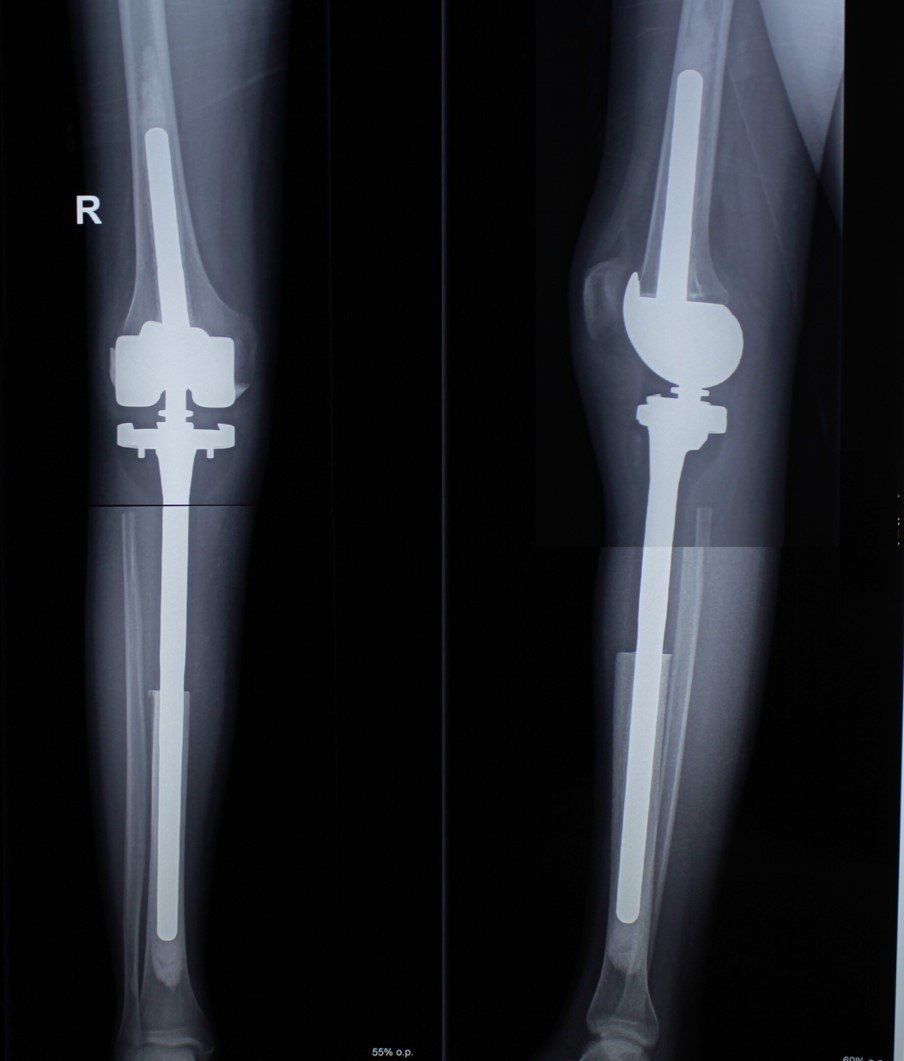

После получения предоперационной химиотерапии в МЦ ''Наири" была проведена органосохраняющая операции – сегментарная резекция верхней трети большеберцовой кости и коленного сустава, замещение образовавшегося костно-суставного дефекта индивидуальным, изготовленным на заказ эндопротезом. В послеоперационном периоде пациент продолжил показанную по протоколам химиотерапию. В настоящее время лечение завершено, признаков прогрессирования заболевания нет, оперированная конечность функционально пригодная, опороспособность полная.

После операции